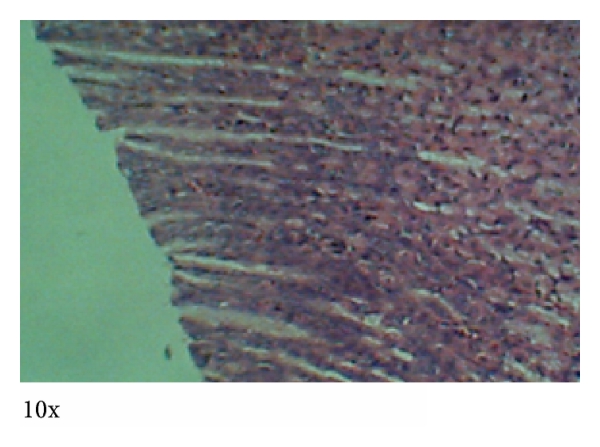

3.4. Histopathology

Photomicrographs of tissues prepared from control and animals treated with MOE at different dose levels are presented in Figures 5–8. No observable cardiomyopathy was noted in the heart (Figure 5). Figure 6 showed no observable ulceration. The epithelial cells of the stomach are intact. Figure 7 also showed no observable histological lesions in the glomerulus and the tubules. There were no observable histological lesions in the sinusoids and central vein of the liver (Figure 8).

Ingestion of chemicals substances including those of plant origin in excess and especially over long periods may adversely affect major organs like the heart, kidney, liver, and even the gastrointestinal system. Thus, the evaluation of histopathological changes in organs remains a cornerstone in assessing the safety of medicines and other substances [30, 31]. Histopathological examinations of the heart and stomach did not reveal any observable cardiomyopathies (Figure 5) and ulcerations of the epithelial cells in the male rats (Figure 6). These findings are consistent with other studies [32]. It might be expected that at high doses of MOE may result in accumulation of MOE-derived iron. This mineral, though an important component of haemoglobin and other proteins and enzymes, may cause gastrointestinal distress, hemochromatosis, and so forth [22, 23]. The absence of these effects may be explained by the fact that the various elements were within normal limits [16].